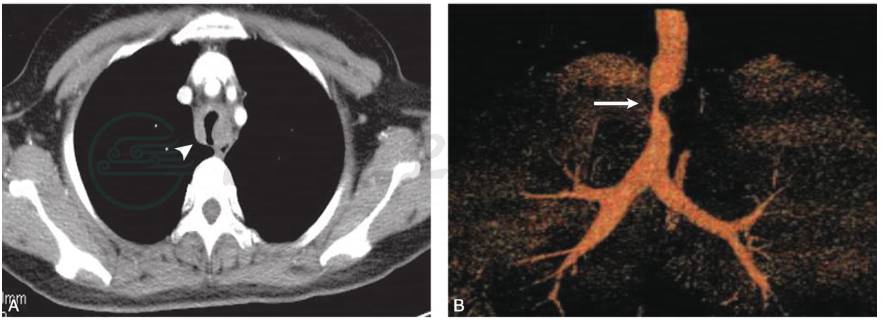

胸部CT增强+气道三维重建(2019-04-07):气管壁环形增厚伴轻度强化,管腔重度狭窄(图 8-37-2)。

图2 胸部CT增强+气道三维重建

A.胸部CT增强示气管中段管壁环形增厚伴轻度强化(箭头);B.气道三维重建示气管管腔呈裂隙样狭窄(白箭)